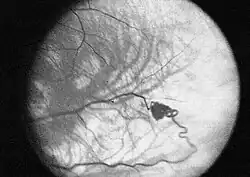

- Die retinalen Hämangiome können eine mehr angiomatöse oder mehr fibrosierende Ausprägung haben. Dies ist für die Prognose der Erkrankung in Bezug auf das Auge sehr wichtig. Bei mehr angiomatösen Hämangiomen überwiegt der Gefäßanteil der Gewebsveränderung, was häufiger zu massiven Einblutungen in das Auge mit einer plötzlichen vollständigen Erblindung führen kann. Fibrosierende Hämangiome verursachen eher eine Traktionsveränderung der Netzhaut. Wenn die Hämangiome in der Peripherie der Netzhaut gelegen sind, verursachen sie häufig keinerlei Beschwerden; liegen sie dagegen zentral, kann bald eine Visusminderung auftreten. Wenn die Gefäßknäuel direkte Verbindungen zwischen Venen und Arterien ausbilden, kann es zum Austreten von Gewebsflüssigkeit im Auge kommen mit den entsprechenden Folgen (Druckerhöhung).

Zum Verlauf der Erkrankung werden sehr unterschiedliche Angaben gemacht. Die retinalen Angiome werden im Durchschnitt bei den Patienten im Alter von 25 aufgedeckt. Die Netzhautveränderungen können, sofern sie rechtzeitig entdeckt werden, gut behandelt werden. Die intrazerebralen und spinalen Hämangioblastome können vor allem im Bereich des Hirnstammes zu gefährlichen Blutungen führen.

Laserkoagulation

Die Laserkoagulation wird zurzeit bei kleineren retinalen Hämangiomen angewendet. Dabei werden Argon-,[10][11] Krypton-,[12] Farbstoff- und Diodenlaser, früher auch Xenon-Koagulator, eingesetzt. Der Vorteil des Verfahrens ist die gezielte Zerstörung mit genauer Dosierung, wobei das gesunde Gewebe geschont wird.[13] Durch häufige Anwendungen der Methode zeigen sich Erfolge bei retinalen Hämangiomen bis zu einer Größe von 4,5 mm, allerdings ist die Therapie am effektivsten bei Größen bis 1,5 mm (entspricht einem Papillendurchmesser) oder kleiner.[14][15][16] Angiome, die größer als ein Papillendurchmesser sind, zeigen bei der Laserkoagulation nur unbefriedigende Ergebnisse und sollten daher mit anderen Methoden behandelt werden.[17] Die Laserkoagulation kann direkt auf das Angiom erfolgen, auf die zuführende Gefäße des Angioms oder beides gleichzeitig.[18] Die Ansprechrate bei der direkten Photokoagulation bei der Benutzung vom Argon-Laser liegt bei 91 – 100 %.[15][19] Hämangiome mit der Größe von einem Papillendurchmesser brauchen durchschnittlich drei Anwendungen bis zur vollständigen Verödung, hingegen ist bei Mikroangiomen eine Sitzung meist ausreichend.[17] Einige Autoren empfehlen die Kombination der Laserkoagulation mit anderen Methoden, um Angiome zu behandeln, die durch die alleinige Laserkoagulation nicht ausreichend behandelt werden konnten.[20]